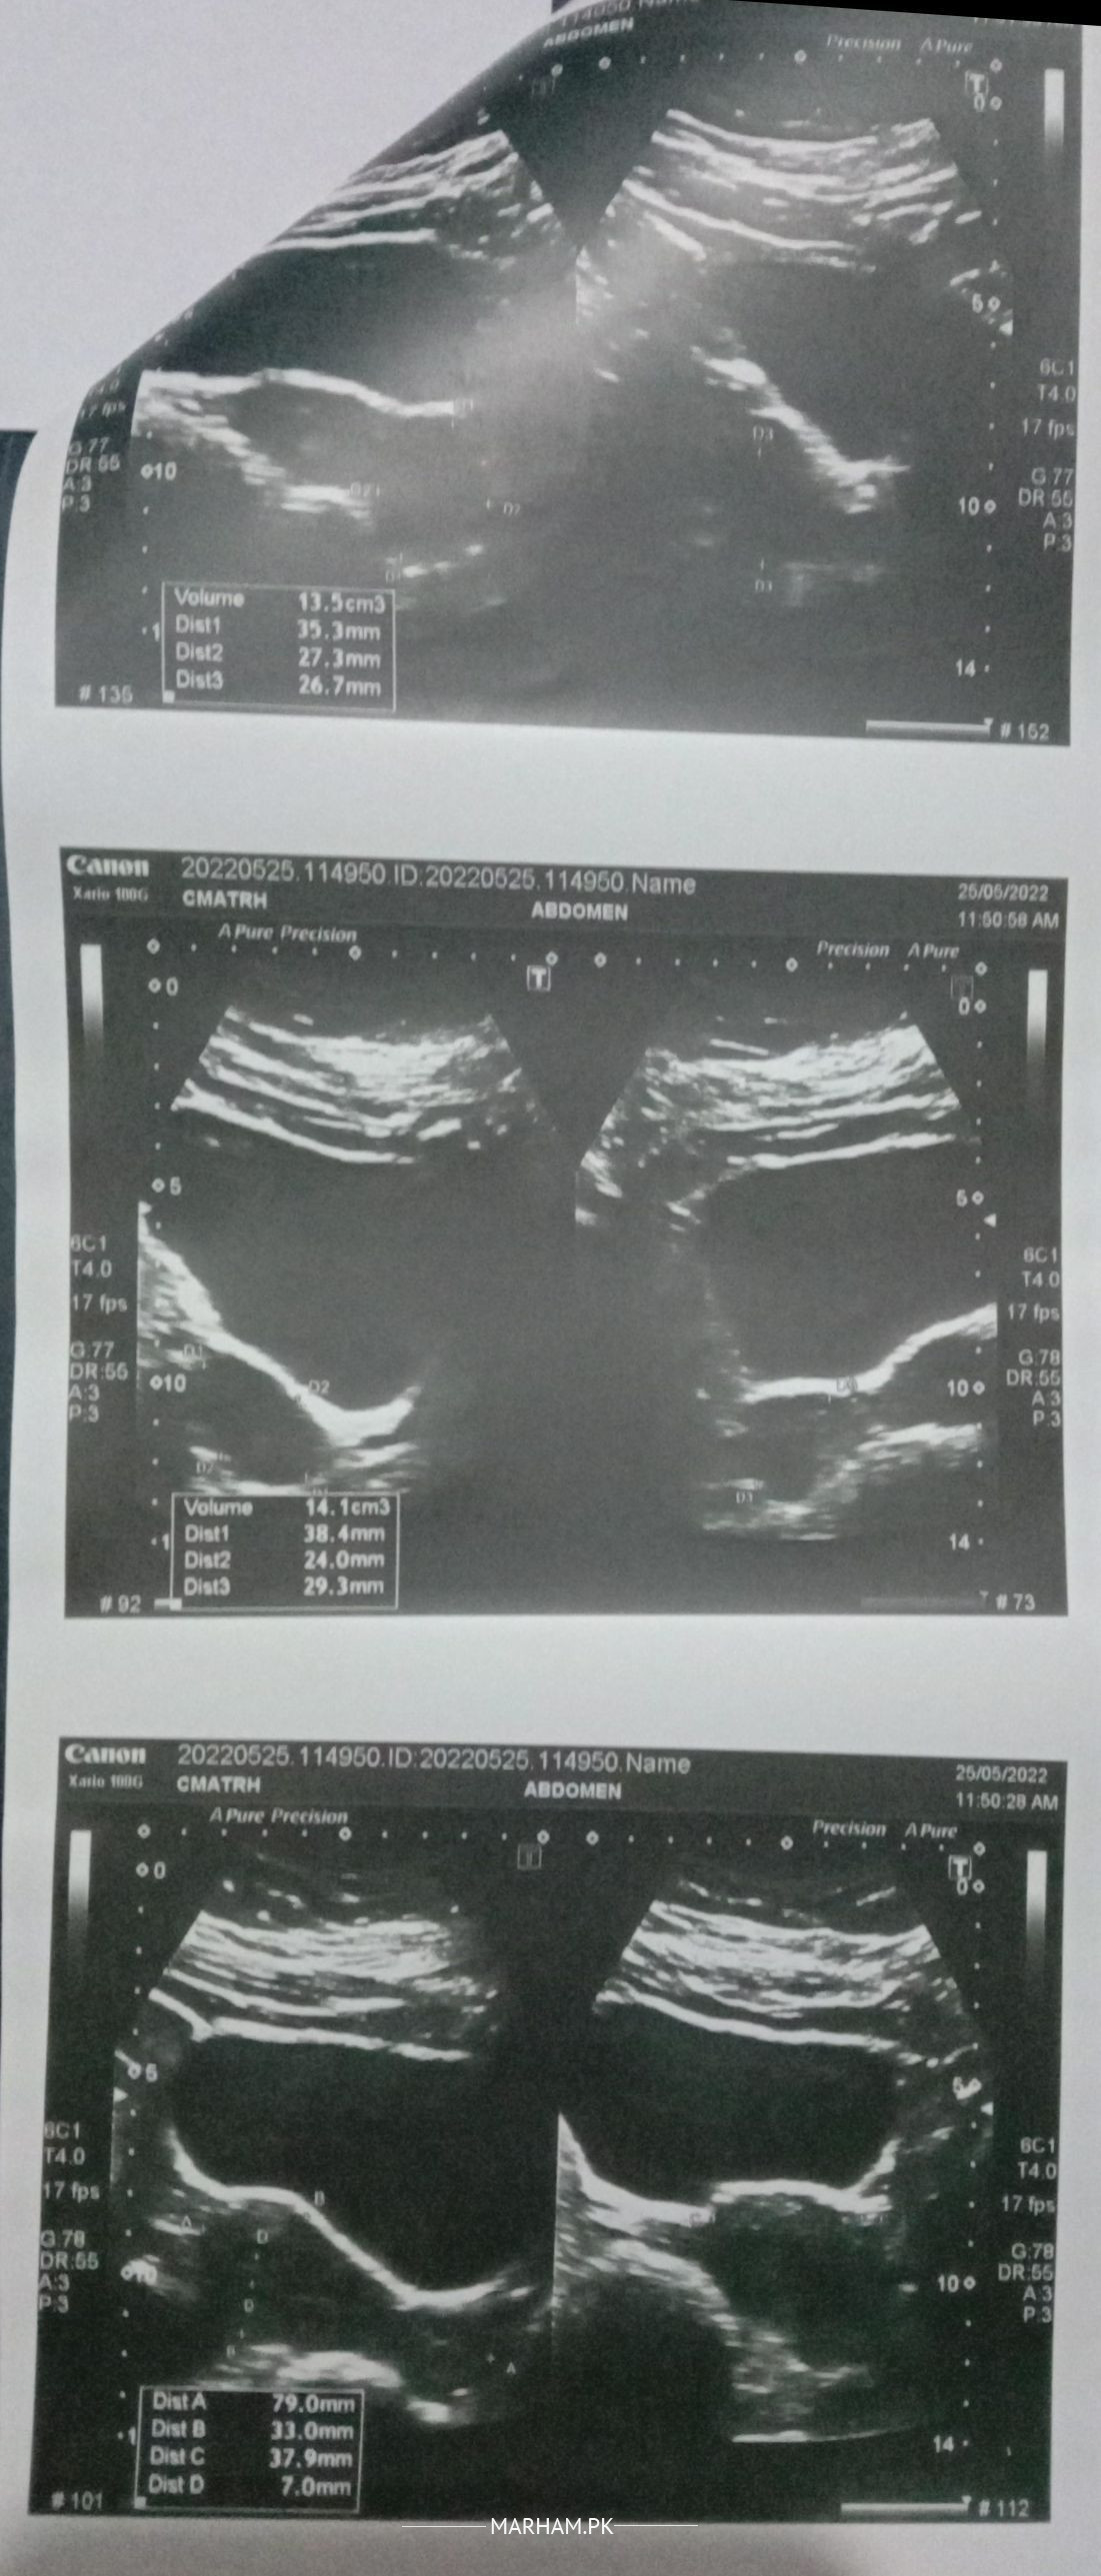

i am 30 years old. 5.5 years married 1 miscarriage second missed miscarriage and third last year induced labor with dnc in 5 month due to no growth after 12 week. i am trying to conceive again but could not. plz explain what ultra sound says having irregular period since 3 months

ur complete workup done at the time of miscarriage like ur Blood group, fasting blood sugar level and some other. ur ultrasound report is normal

my blood group is o+ my sugar level are always normal no gestational diabates etc just had some high bp issue some times. why there is no follicles seen in ultrasound?